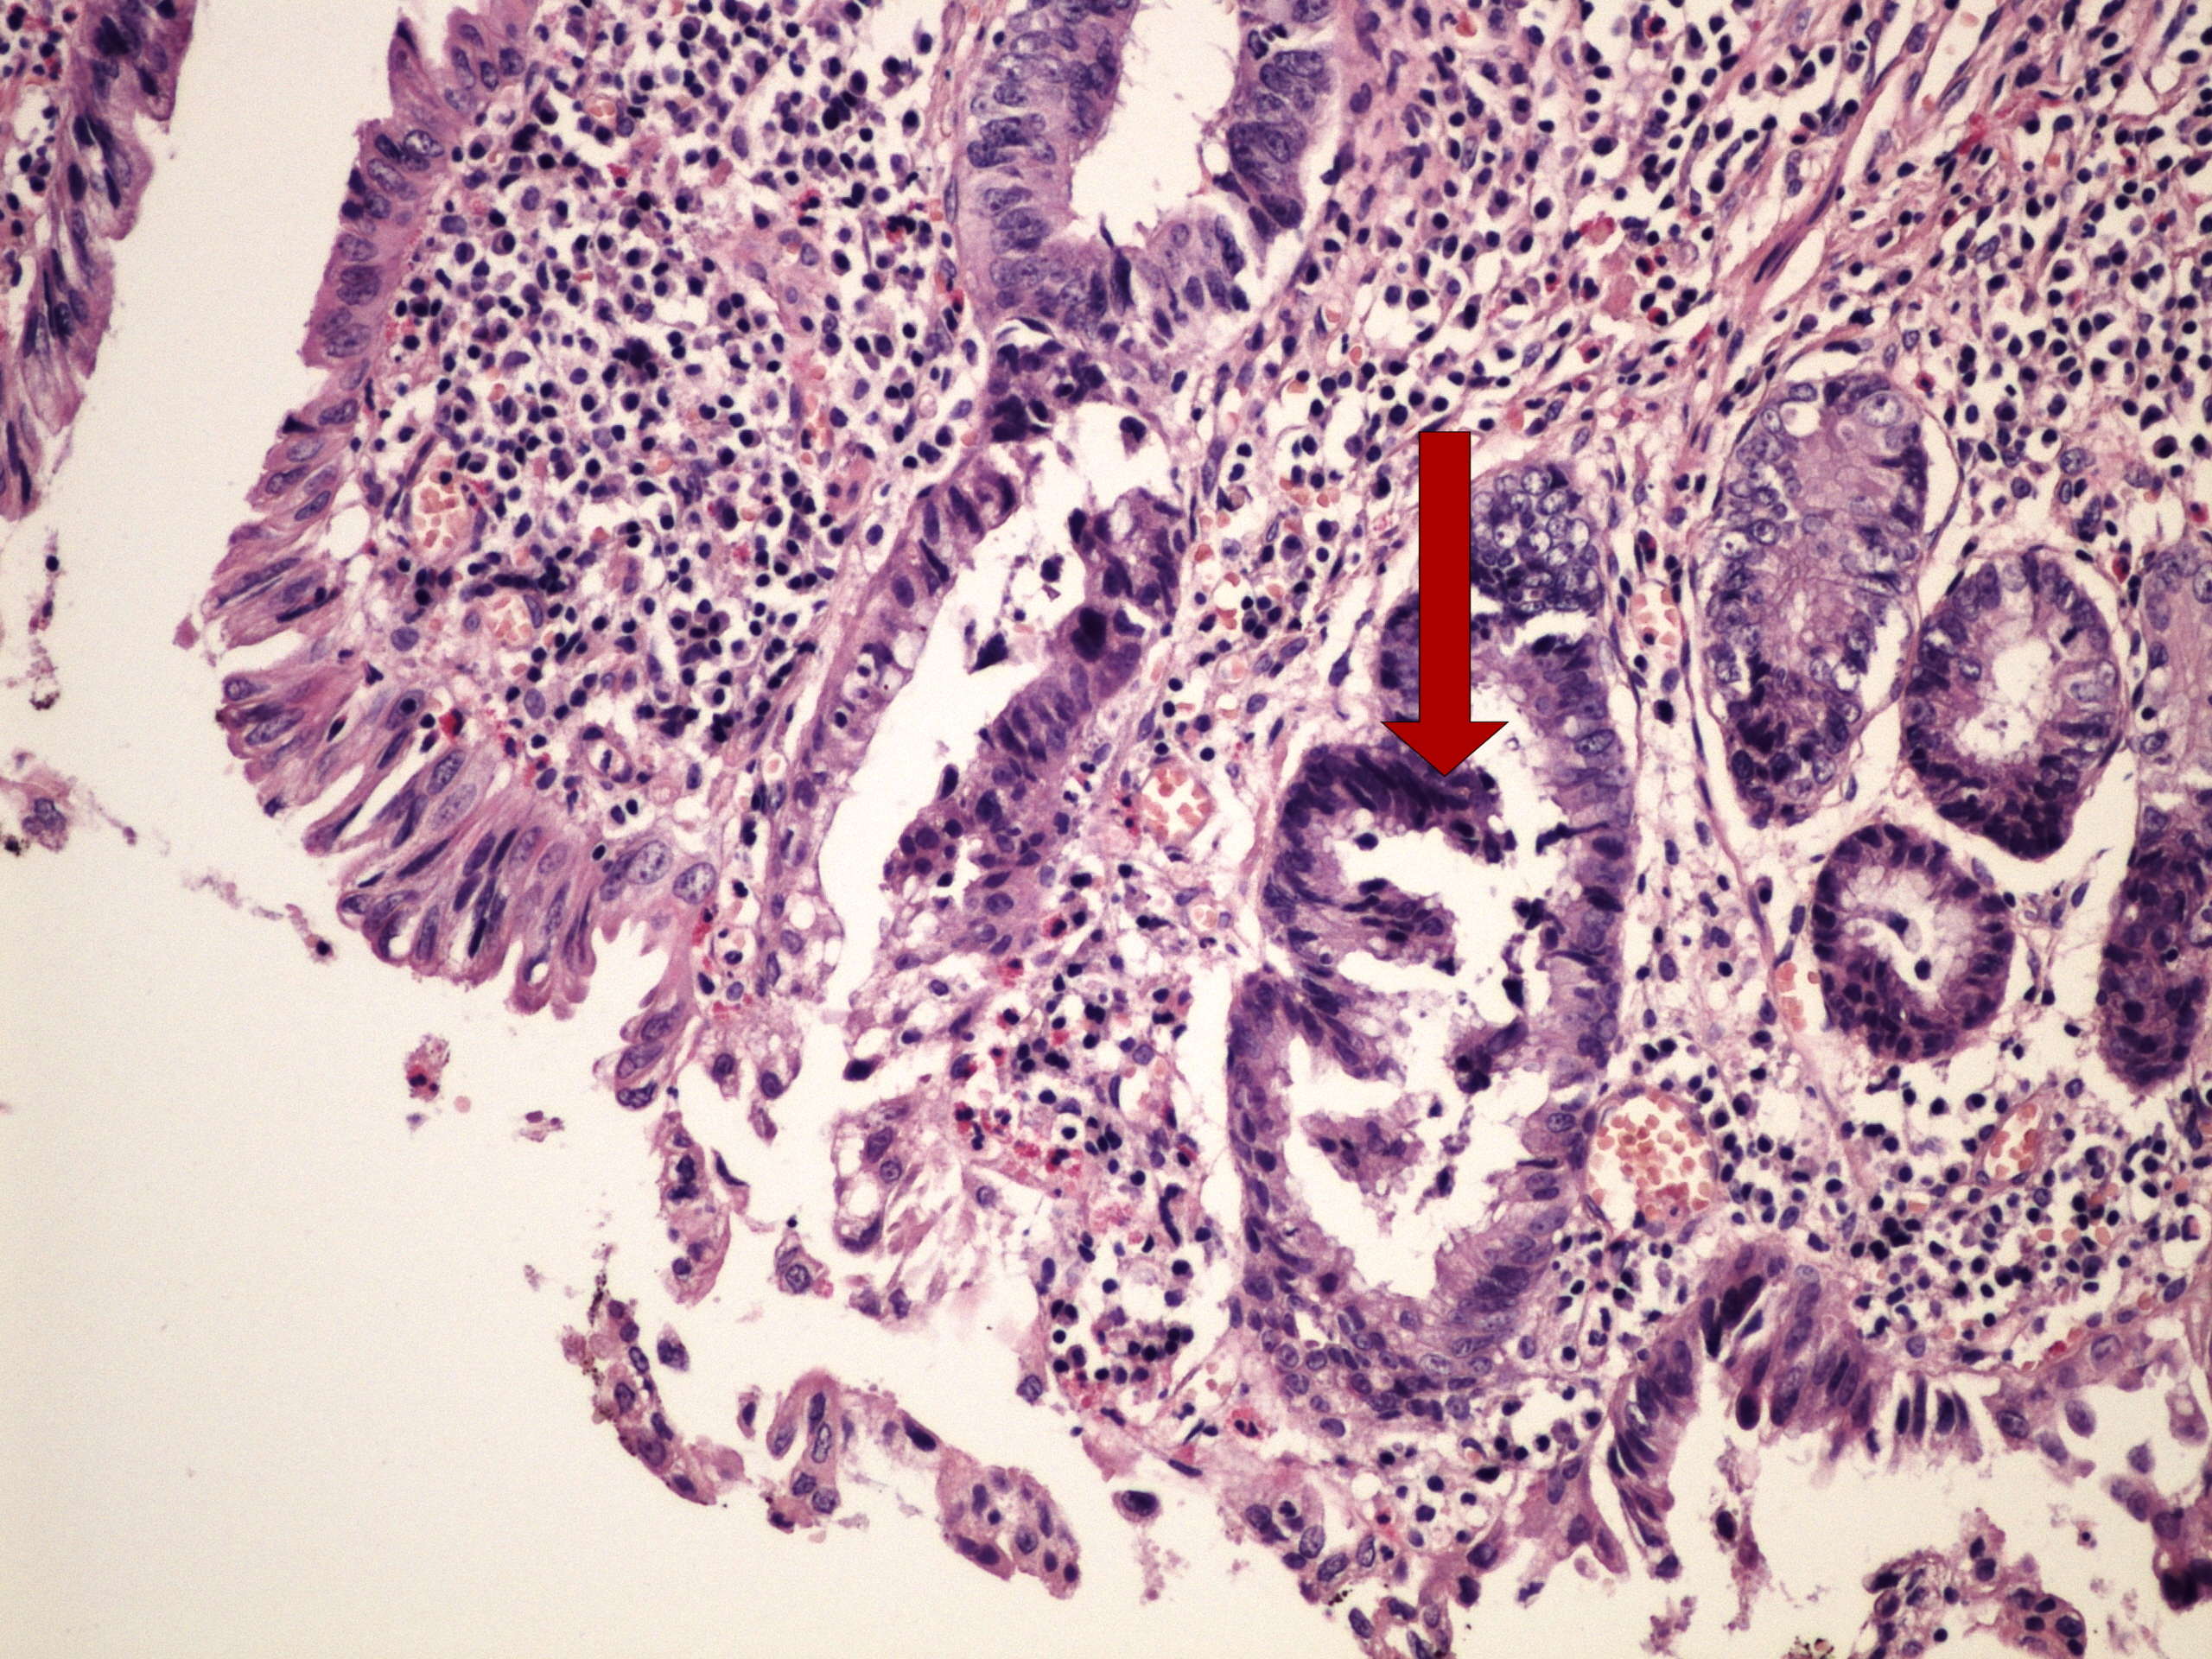

Preparát č.19 a č.20 - branchiogenní cysta

Struktury

- zánětlivý infiltrát

- dlaždicový epitel (stěna cysty)

- lumen cysty

- epitel bez atypií